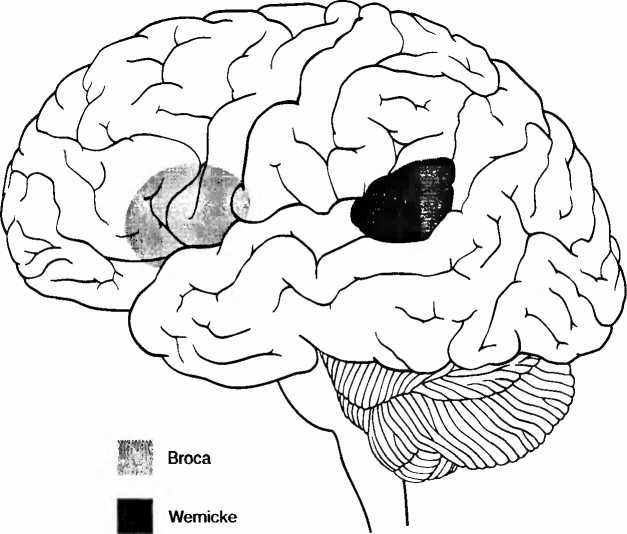

Рис. 6. Справа — томограмма мозга сильно запущенного трехлетнего ребенка, и для сравнения — томограмма мозга ребенка такого же возраста с нормальным развитием мозга (слева). У запущенного ребенка мозг значительно меньше, с увеличенными желудочками вентрикулами, полостями, черного цвета), по сравнению с мозгом нормально развивавшегося ребенка того же возраста. Кроме того между мозговыми извилинами видны увеличенные пространства из-за сморщивания (атрофии) коры больших полушарий (В. D. Perry, 2002).

Наше окружение в течение первых лет после появления на свет определяет строение систем мозга, ответственных за речь. Позднее, после критического периода развития систем речи, когда мы пытаемся говорить на другом языке, в нашем мозгу уже запечатлен родной язык, и это приводит к появлению акцента. Области мозга, обрабатывающие слова и визуальную информацию, у детей 9-11 лет еще перекрывают друг друга. У взрослых происходит специализация, и оба вида информации обрабатываются в отдельных областях мозга. Языковая среда ведет к образованию неизменных различий в структурах и функциях мозга. В зависимости оттого, является ваш родной язык японским или одним из западных языков, гласные звуки и звуки животных обрабатываются в левом или в правом полушарии, вне связи с вашим генетическим происхождением. В лобной доле коры головного мозга лежит речевая зона Брока (рис. 7) Если взрослый человек учит второй язык, внутри ее используется другой субареал. Но если ребенок растет как двуязычный, оба языка используют одни и те же фронтальные области. Левое хвостатое ядро (nucleus caudatus, рис. 26) контролирует, какая именно речевая система мозга используется. Язык и культурное окружение определяют не только, какие системы мозга заняты обработкой речи, но и как именно могут интерпретироваться выражения лица; как люди привыкли, окинув взглядом, схватывать образ и то, что их окружает. Так, японцы и жители Новой Гвинеи не могут хорошо различать, выражает лицо страх или удивление, а китайцы, в противоположность американцам, сосредоточивают внимание не только на наиболее важном предмете, но рассматривают его в отношении с непосредственным окружением. При подсчете людей китайцы используют частично и другие области мозга, нежели англоговорящие люди Запада. И те и другие пользуются теми же арабскими цифрами и используют ту же нижнюю часть теменной доли коры головного мозга (рис. 1). Но англоговорящие, кроме того, больше используют речевые системы для обработки чисел, тогда как у китайцев в большей степени задействованы визуально-моторные системы. Это объясняется тем, что китайские дети растут, изучая иероглифы. Китайские счеты суаньпань больше не играют сколько-нибудь заметной роли в современном Китае.

Рис. 7. Речевые центры Брока (лобный, владение речью) и Вернике (височный, понимание речи). Эти центры также тесно связаны с восприятием музыки и пения. Музыка и речь очень близки друг к другу.